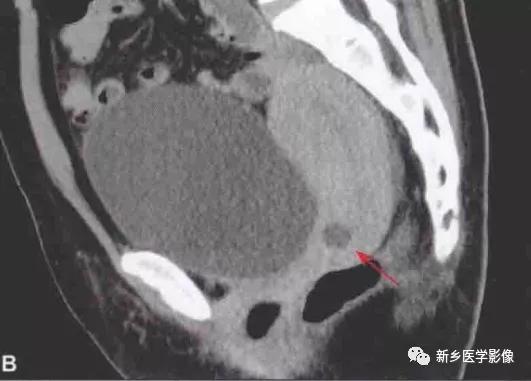

CT表现:平扫如无合并症,与宫颈密度相近或低于 宫颈密度

增强扫描时表现为宫颈圆形的低密度区, 无强化;大的囊肿与宫颈内膜腺体肿瘤相似;囊肿罕见凸岀于宫颈壁外